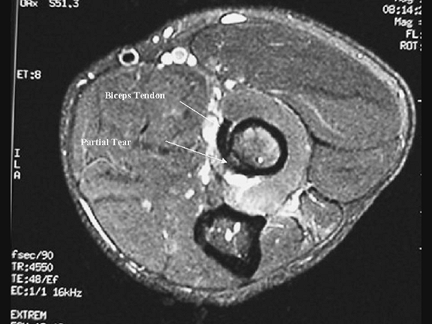

partial tears, however, MRI evaluation is very helpful is assisting in

the diagnosis of these cases. The presence of increased intratendinous

signal intensity and abnormal tendon diameter along with fluid around

the tendon can confirm the diagnosis (Fig. 52-2).

![]() |

|

Figure 52-2

Axial MRI image from a patient with a partial distal biceps tendon tear demonstrating increased signal intensity at the tendon insertion site coinciding with the site of the tendon tear on the radial surface of the tendon. (Reprinted from Kelly

EW, Steinmann SP, O’Driscoll SW. Surgical treatment of partial distal biceps tendon ruptures through a single posterior incision. J Shoulder Elbow Surg. 2003;12:456–461 , with permission.) |